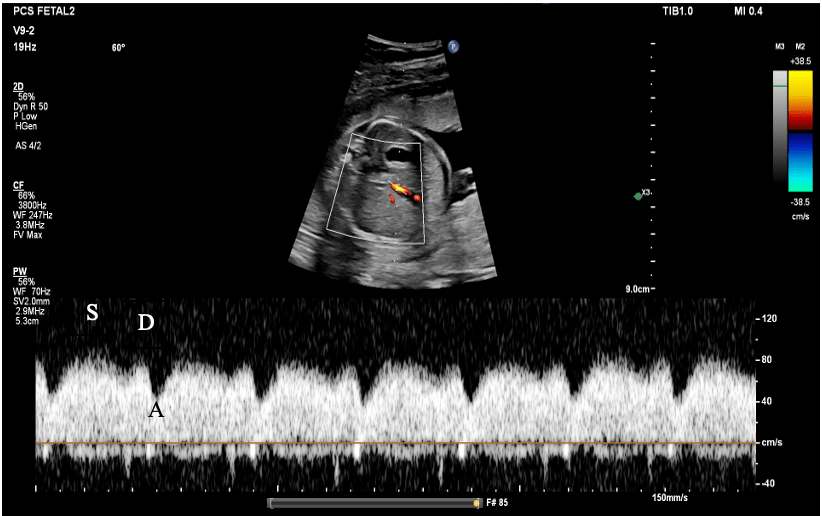

Understanding the Ductus Venosus Waveform The analysis of the Doppler waveform of the ductus venosus reveals three crucial phases:

- S-wave (Systole): This represents forward flow during ventricular systole, highlighting the peak positive wave as the heart contracts.

- D-wave (Diastole): Occurring during early diastole as the ventricles relax, this wave indicates forward flow with a magnitude typically smaller than the S-wave.

- A-wave (Atrial Contraction): This crucial wave denotes forward flow during atrial contraction, illustrating the pressure differential between the right atrium and the ductus venosus.

- S-wave: Notably prominent and positive.

- D-wave: Positive, though generally smaller than the S-wave.

- A-wave: Maintains a position above the baseline, indicating healthy atrial contraction and an adequate pressure gradient.